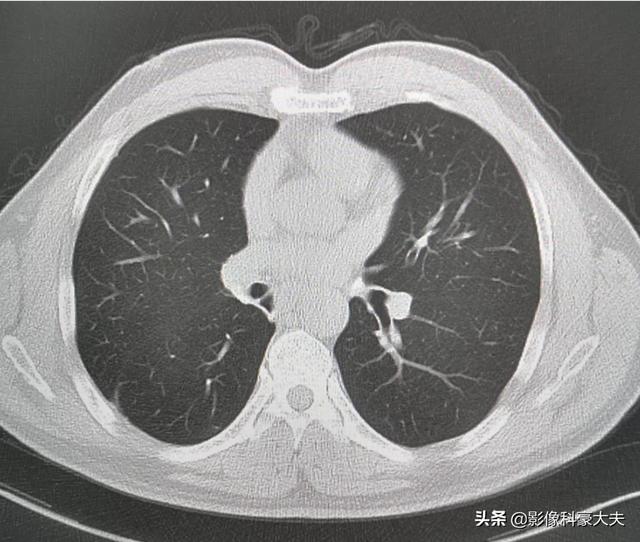

肺結節の手術からの回復は、手術の種類にも関係する。

肺葉下切除(分葉切除や楔状切除)は、切除される肺組織が少なく、正常な肺組織が多く残るため、肺機能への影響が少ない。肺組織がより多く切除されるため肺葉切除術が行われた場合、正常な肺組織が相対的に少なくなり、肺機能への影響が大きく、胸部不快感を引き起こしやすくなります。次の写真は2種類の肺切除の肺を示しています。 上の写真は右下肺結節肺葉切除術で、術後右肺がかなり小さくなっているのがわかります。下の写真は左下肺結節の肺葉下切除術で、術後左肺が大きくなっているのがわかります。